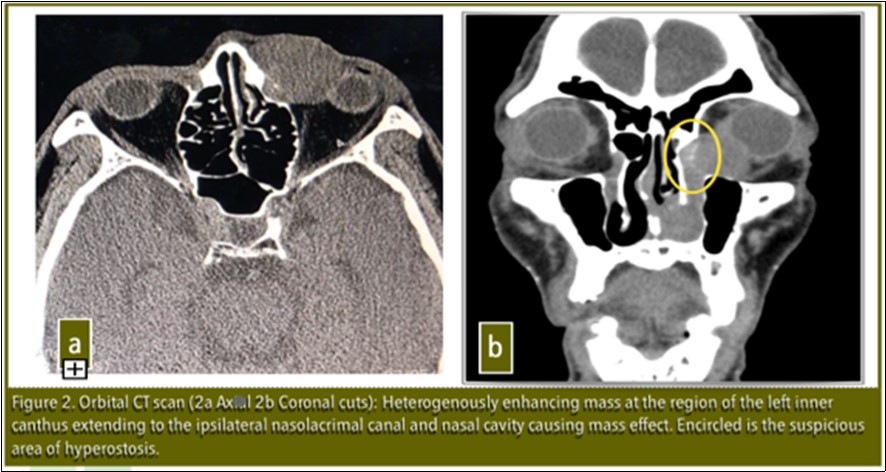

Visual acuity, slit lamp examination, extraocular eye muscle movements were unremarkable at the time of examination except for lacrimal apparatus irrigation which showed blockage at the level of the left common canaliculus. Orbital CT-scan revealed: Heterogenously enhancing mass extending to ipsilateral nasolacrimal canal and nasal cavity causing mass effect. No bone erosions present. There was note of a suspicious area of hyperostosis in the area of the lacrimal sac [Figure 2]. Patient was referred to the Department of Otolaryngology Head and Neck Surgery for co-management. Punch biopsy was done and histopathology revealed Inverting Papilloma.

Figure 2.Orbital CT scan ( 2a Axial. 2b Coronal cuts): Heterogenously enhancing mass at the region of the left inner canthus extending to the ipsilateral nasolacrimal canal and nasal cavity causing mass effect. Encircled is the suspicious area of hyperostosis.

It is important to determine the area of origin by CT scan to optimize the proper surgical management and prevent recurrence.3Lee et al in his paper in 2007 noted that there is a high correlation between the origin of the inverted papilloma and focal hyperostosis on CT scan which might facilitate prediction of tumor origin.3

In our patient, hyperostosis was noted in the area of the lacrimal sac on CT scan which was clinically correlated intraoperatively with adhesion of the mass to the bone in the lacrimal sac. This is further evidence that the origin of this tumor is in the lacrimal sac.

Focal hyperostosis on CT scan and intraoperative findings of adhesions highly suggest origin of this tumor to be in the lacrimal sac.